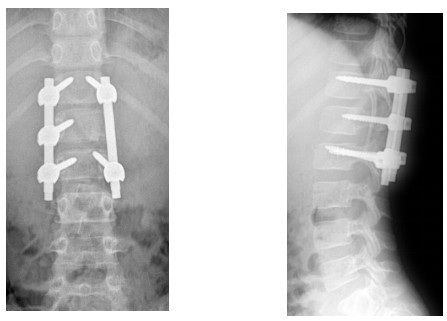

10歲小孩術(shù)前增強MR

術(shù)后復(fù)查不固定位置良好